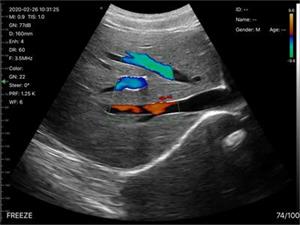

C6无线多普勒超声诊断仪

[ 猫、狗、牛、马、老鼠、异宠 ]

数字成像技术,清晰的图像,高性价比

无线连接,操作简单轻便,携带方便